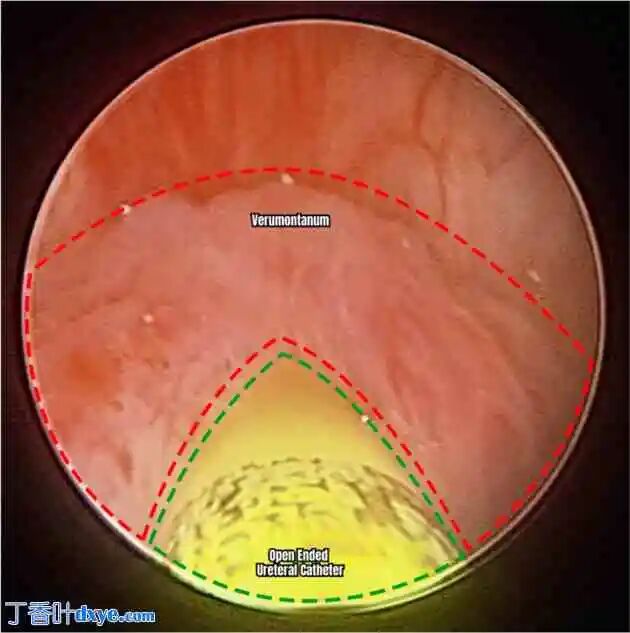

手术当天,患者接受全身麻醉。初始膀胱镜检查发现 PUC 开口于精阜中线。使用 French 5 开口导管将插管插入通向 PUC 腔的精阜。插入儿童膀胱镜直接观察和评估囊肿及其内容物,囊肿内少量充满沉积物。将开口导管置于 PUC 内以便于腹腔内识别(图 2、图 3)。其他关于前列腺囊肿切除术的研究表明,将膀胱镜留在囊肿内,因为膀胱镜末端的光线可作为其位置的视觉引导,以及在切除过程中在腹腔内操纵囊肿的一种方法。将 12 毫米机器人摄像头端口插入脐上区域,同时在每个半腹部放置另外两个端口以形成 W 形配置。采用经腹后入路进行腹膜剥离,暴露精囊和输精管。仔细识别双侧输精管,并将其从侧面插入 PUC 的顶端。作者之前在腹腔镜手术中完成的两例病例也出现过这种情况。此外,由于输精管插入,必须结扎输精管才能切除。沿环状剥离并游离 PUC。沿尾部剥离 PUC 底部最终将其插入尿道。在膀胱镜检查中,将 PUC 的顶部掀开,露出先前插入的开口导管,随后将其切除(图 4)。仔细剥离,确保留下至少 1 厘米的囊肿,以防止损伤和扭曲尿道和膀胱颈。用连续 Vicryl 缝线修复缺损。通过摄像端口送入切除的标本(图 5)。术后留置Foley导尿管。随后关闭腹腔镜端口。手术持续122分钟,估计失血量为20毫升(补充视频)。

图2

膀胱镜视图:使用5Fr开口导管插入精阜,进入前列腺囊肿腔。